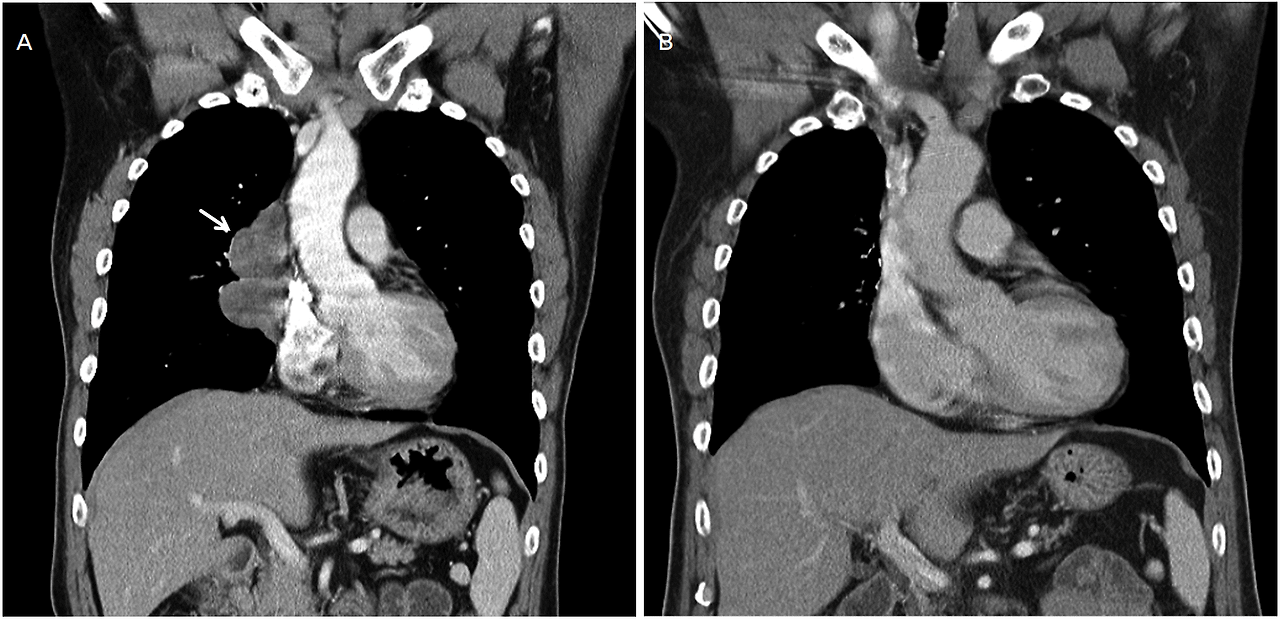

- 첫째, 병기입니다. 흉선암은 주변 장기(폐, 심장막, 대혈관)와 가까운 위치에 있어 국소 침윤이 비교적 쉽게 일어날 수 있고, 림프절이나 다른 장기로 전이가 생기면 치료 전략이 달라집니다.

- 둘째, 수술로 완전 절제가 가능한지(R0 절제 여부)입니다. 흉선암은 수술이 가능할 때 예후가 확 좋아지는 경향이 있으며, 수술이 어렵거나 불완전 절제가 예상되는 경우에는 항암-방사선의 비중이 커집니다.